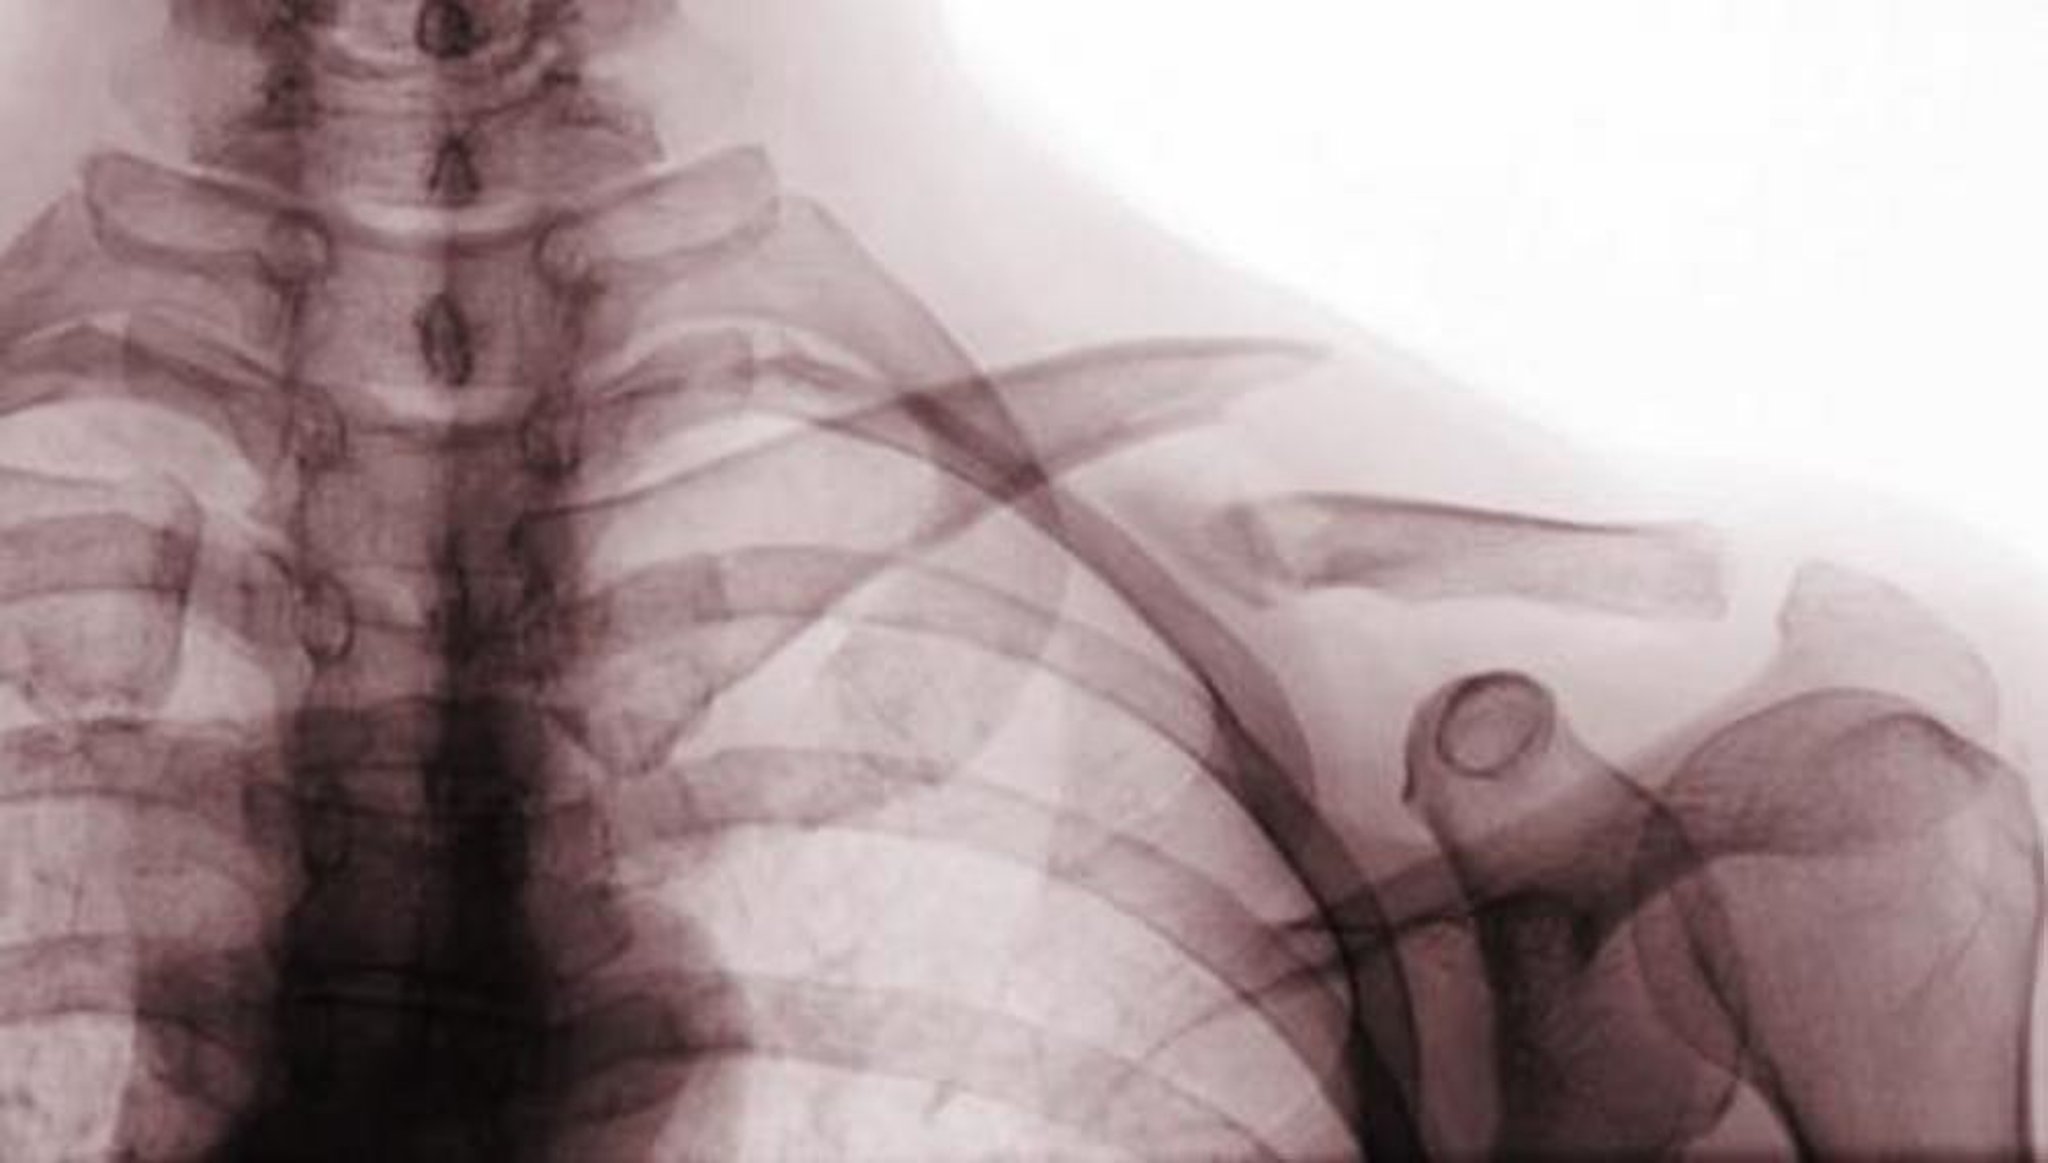

Fracture de la clavicule

Cette radiographie de face montre une fracture déplacée du tiers moyen de la clavicule (fracture de classe A).

Scott Camazine/SCIENCE PHOTO LIBRARY